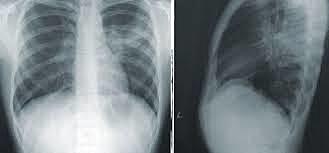

The photographic plates were used to demonstrate that the objects could be more or less transparent to X-rays , So this way

the first human radiographs emerged.